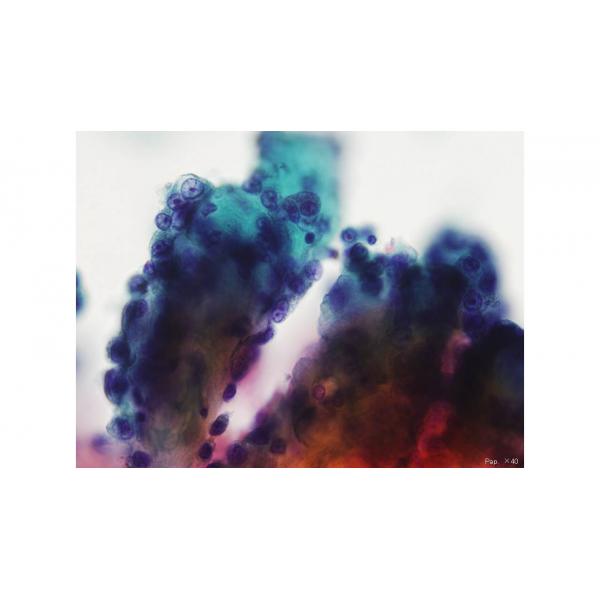

第31回日本臨床細胞学会九州連合会学会スライドカンファレンス症例 2

種別:呼吸器

出題:長崎大学病院 病理診断科 木下 直江 先生

| 年齢 | 70歳代 | 性別 | 男性 |

| 採取部位 | 肺 | 採取方法 | 肺胞洗浄液 |

臨床所見

既往歴:

造船業に従事し40年以上のアスベスト暴露歴あり。

20歳から40歳まで20本/日の喫煙歴あり。

5ヶ月前より労作時呼吸困難と湿性咳嗽あり。1ヶ月前にX線検査で右胸水貯留あり。CT検査で右中葉の結節影あり。

現病歴:

前医で上記所見を認め精査目的で当院内科へ紹介入院となった。

| 正解 | 3.上皮型中皮腫 |

▼選択肢及び投票結果

| 1.腺癌 | 42件 | (30.4%) | |

|---|---|---|---|

| 2.大細胞癌 | 8件 | (5.8%) | |

| 3.上皮型中皮腫 | 33件 | (23.9%) | |

| 4.反応性肺胞上皮 | 53件 | (38.4%) | |

| 5.悪性黒色腫 | 2件 | (1.4%) | |

| 投票総数 | 138件 | (100%) |